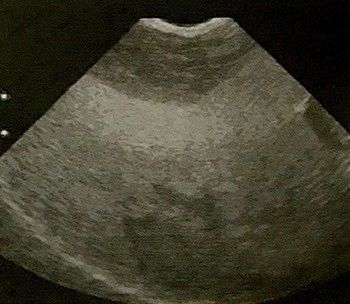

【诊断】根据生活史、临床症状,结合实验室检查(血脂增高,ALP明显升高,高胆红素血症,ALT和AST通常也增高,但增高幅度不大)、组织病理学检查(肝脏活体组织检查)及B超检查 (肝脏回声弥散性增强,肝脏肿大)等,可作出诊断(图12、图13)。

图13 脂肪肝综合征

B超检查。肝脏形态稍大,实质显示微细致密的散射光点或“大片雪”样肝实质回声